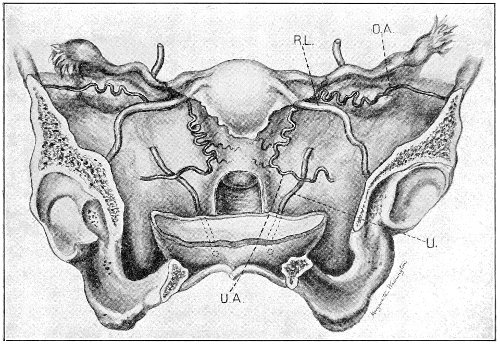

An accurate knowledge of the anatomy and mechanism of the female perineum is essential to an understanding of the nature and treatment of injuries to this structure. The anatomical structures lying between the anus behind and the symphysis pubis in front are those that most directly interest the gynecologist. Proceeding from 57 below upward, we find the following structures lying in superimposed planes: the skin, the superficial fascia, the deep layer of the superficial fascia, the transversus perinæi and the sphincter vaginæ muscles, the anterior layer of the triangular ligament, the posterior layer of the triangular ligament, the levator ani muscle (Fig. 19).

Fig. 18, A.—Superficial structures of the female perineum (Weisse).

Fig. 19.—Dissection of female perineum: on the left side the perineal muscles are exposed by the reflection of the perineal fascia; on the right side the muscles and the superficial layer of the triangular ligament have been removed, thereby exposing the deep layer of the ligament. S. V., Sphincter vaginæ muscle.

The vagina passes through these structures. They surround and support the ostium vaginæ as the fascia and muscles surround and support the opening of the rectum or the anus. The muscles and fasciæ are attached in the median line between the anus and the vagina, and therefore this part of the body, which is called the perineum, is supported or maintained in its 58 proper position by these various structures. The transversus perinæi arises from the ramus of the ischium and is inserted in the perineum. The bulbo-cavernosus, or sphincter vaginæ, arises in the perineum and is inserted in and about the clitoris. The inner fibers of the levator ani arise from the symphysis pubis and are inserted in the perineum and the lower part of the vagina (Fig. 20). When these muscles contract, their action, therefore, is to draw the perineum upward and forward. At the same time the anus is drawn upward and forward, and so also is the posterior margin of the ostium vaginæ and the lower portion of the posterior vaginal wall.

Fig. 20.—Dissection of female perineum, showing the deeper structures after removal of the levator and sphincter ani muscles.

The vagina has no circular sphincter like the anus, but 59 the vaginal month is kept closed by the action of the transversus perinæi, sphincter vaginæ, and levator ani muscles, which draw the perineum forward, and thus keep the posterior vaginal wall in apposition with the anterior wall.

Fig. 21.—Muscular floor of the pelvis seen from above.

This sling of muscles and fascia, which surrounds and supports the opening of the vagina, may readily be felt in the nulliparous woman by introducing the finger in the vagina and pressing backward and outward toward the ischio-rectal fossa. We then feel plainly, immediately within the ostium vaginæ, a firm resisting band of tissue, apparently about half an inch broad, embracing the posterior portion of the lower vagina. This band is formed by the inner edges of the various muscles and planes of fascia that have been described.

Fig. 22.—Sagittal section showing relations of the several layers of fascia within the pelvic floor (Dickinson).

The vagina extends, as a transverse slit in the pelvic floor, upward and backward, approximately in the direction 60 of a line drawn from the ostium vaginæ to the fifth sacral vertebra. It is approximately parallel with the conjugate of the brim, so that when the woman is erect the long axis of the vagina is inclined at an angle of 60° to the horizon. The vagina is not a vertical open tube: it is a slit in the pelvic floor, in health always closed by the accurate apposition of the anterior and posterior walls (Fig. 21). The anterior vaginal wall is about 2½ inches long in a vertical mesial line. The posterior vaginal wall is about 3½ inches long. The vaginal walls are triangular in shape, being broader above than below. The shape of the normal vagina at the pelvic outlet is shown by Fig. 23. The section here shows the vaginal 61 slit of the shape of the letter H. The portions of the slit extending backward and somewhat outward are called the vaginal sulci or furrows. They are directions of diminished resistance in which tears are liable to occur.

Fig. 23.—Section illustrating the characteristic form of the vaginal cleft (Henle): Ua, urethra; Va, vagina; L, levator ani; R, rectum.] 62